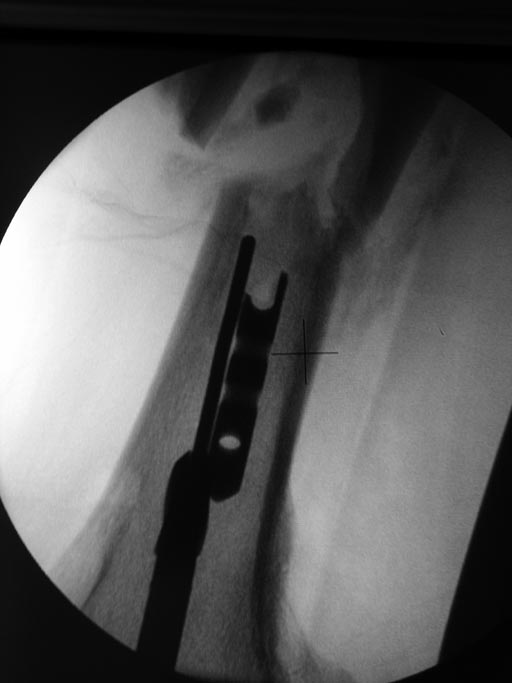

Всем спасибо! Что мы сделали: удалили прокссимальный фрагмент без проблем. Дистальный: через сустав рассверлен канал 13мм. до дистального фрагмента. Который затем удален через тот же канал при помоши загнутой спицы, без особых проблем. Далее ретроградный остеосинтез гвоздем №10.